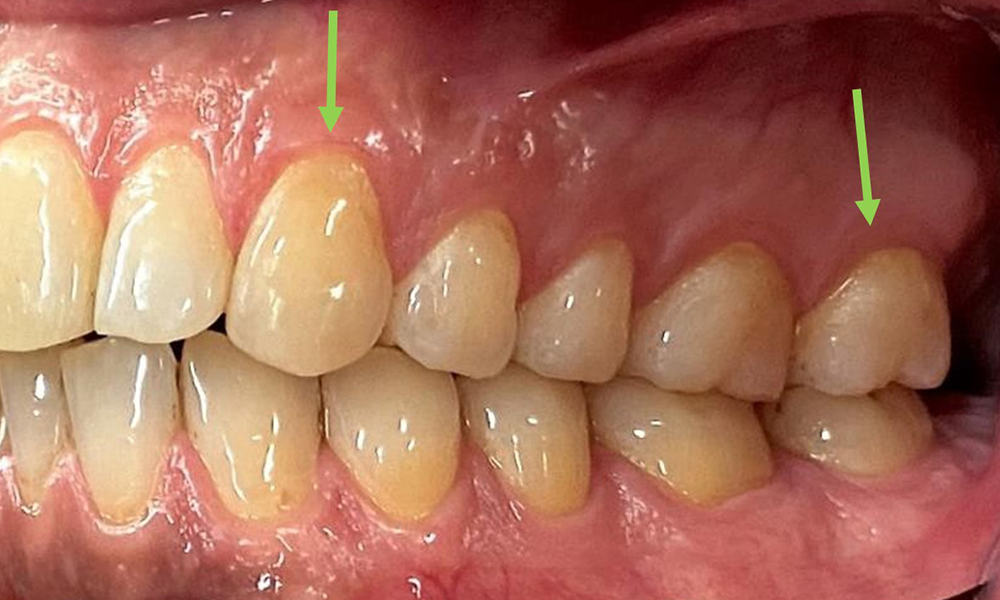

L'instruction et la motivation sont des éléments importants de ces rendez-vous. Il est important que les patients comprennent et adoptent un bon comportement en matière d'hygiène intrabuccale à domicile. L'accumulation de plaque est particulièrement évidente dans les régions cervicales (Fig. 8).

Les flèches indiquent les accumulations de plaques dans la région cervicale.

Fig. 8: Les flèches indiquent les accumulations de plaques dans la région cervicale., © Dr R. Krapf

Il convient d'en discuter avec le patient et d'améliorer la technique de brossage des dents. Il est recommandé d'utiliser une brosse à dents souple pour l'hygiène intrabuccale à domicile en raison de la présence d'érosions et d'attritions.